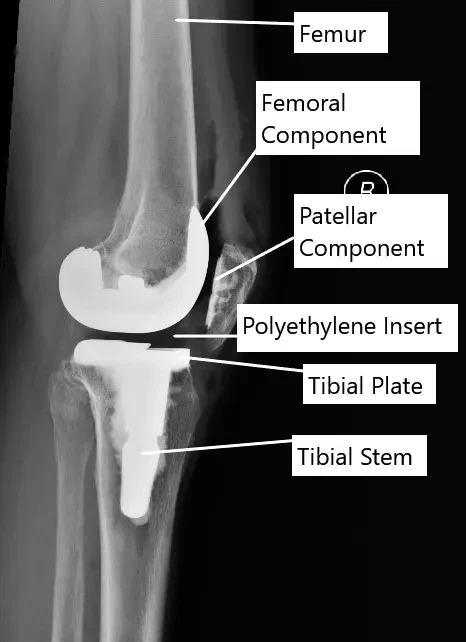

Procedimiento y materiales

La cirugía de reemplazo articular consiste en reemplazar o rehacer la superficie de las partes dañadas de la articulación. Las fuerzas de los tejidos que actúan sobre las articulaciones están equilibradas. Las partes protésicas/artificiales se fijan luego al hueso reasfaltado con o sin cemento.

Las partes protésicas que forman la articulación pueden estar hechas de aleaciones de titanio, cobalto-cromo, polietileno, cerámica o acero inoxidable. La articulación protésica se fija bien con cemento óseo especial o se coloca por presión en el hueso. Los implantes de presión permiten que el hueso crezca sobre ellos.